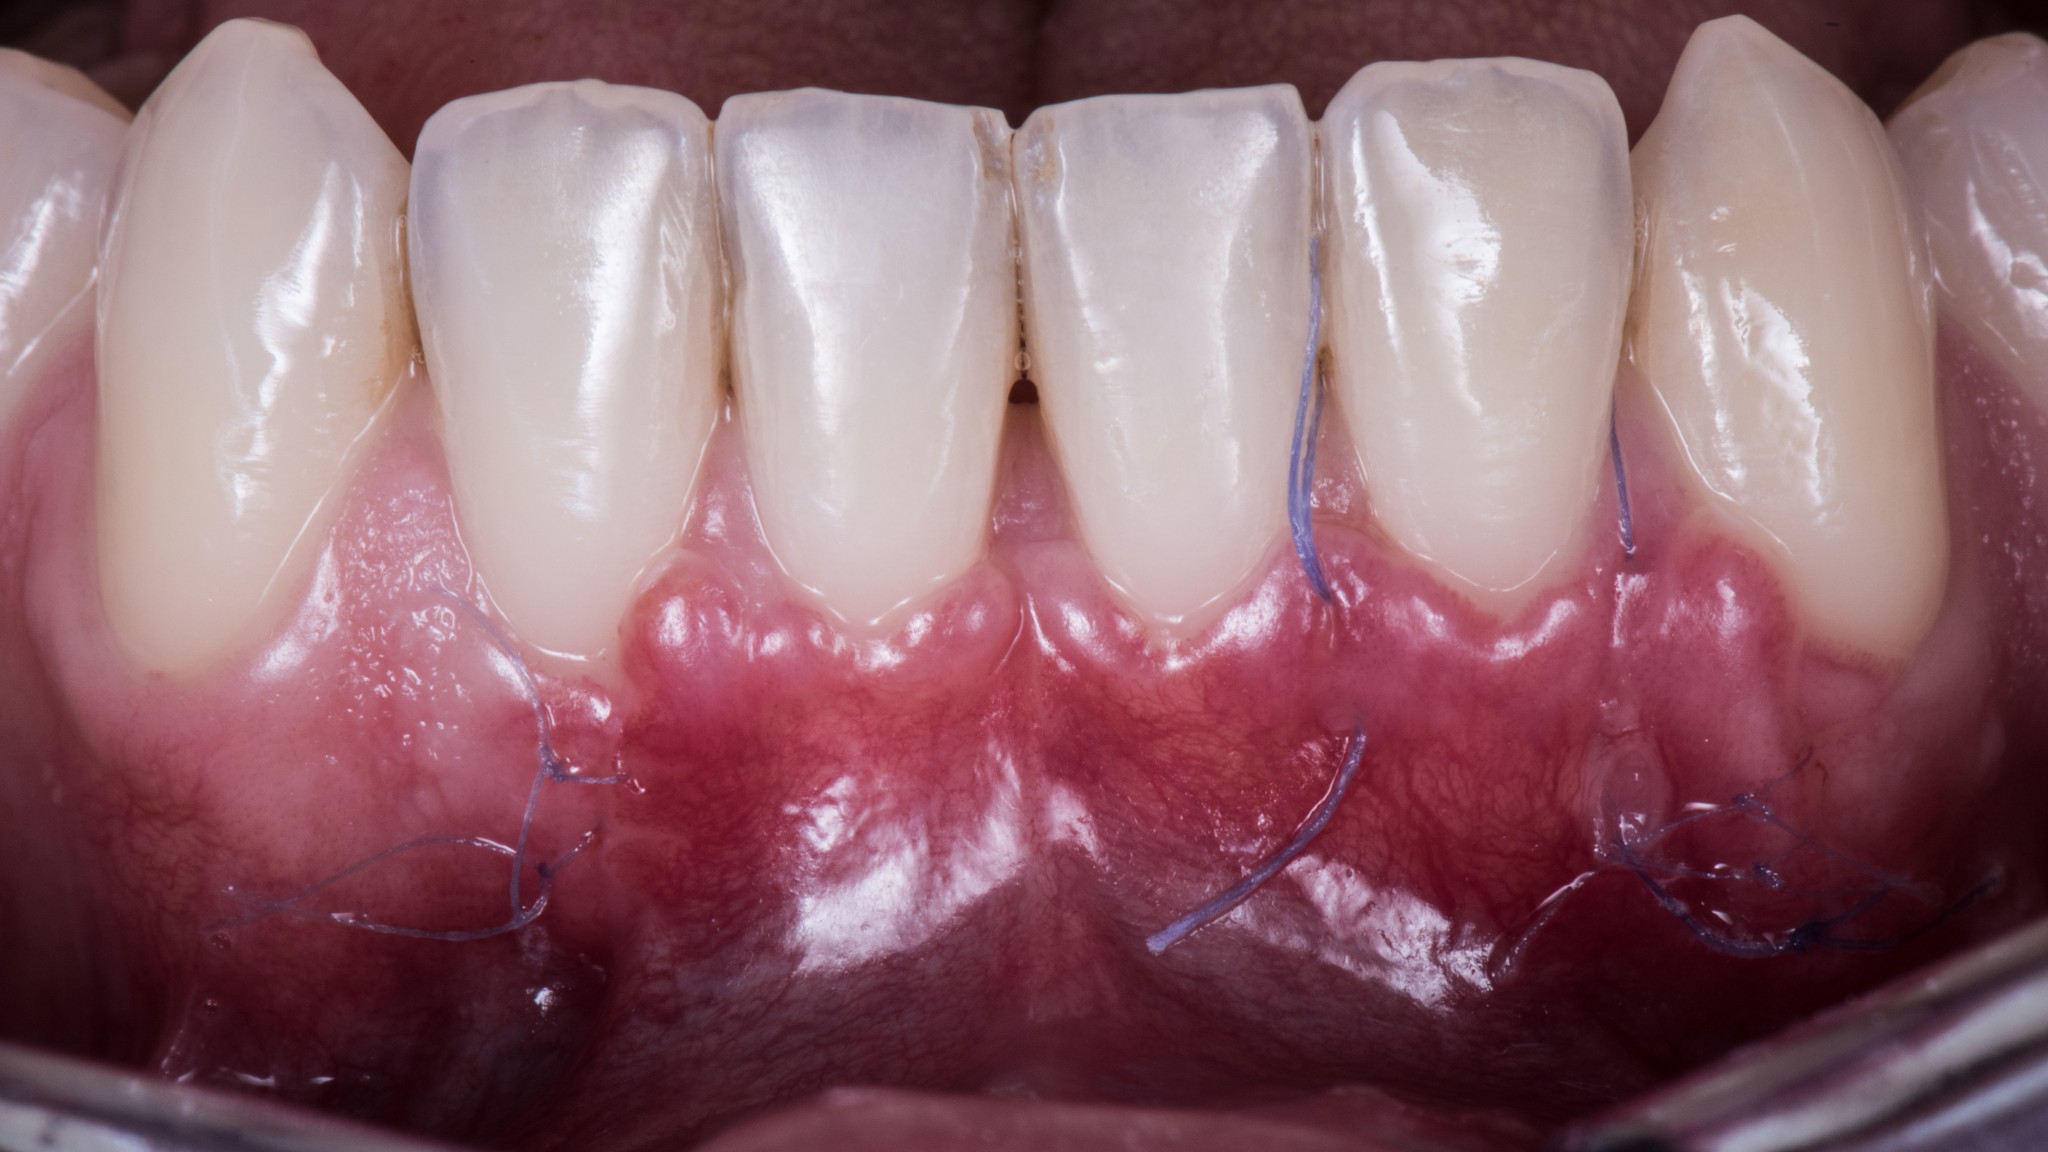

Questo, associato alle altre due tecniche segrete di cui parleremo nei prossimi articoli, ti consente di arrivare a 15 giorni dall’intervento in questa situazione:

Ma soprattutto di arrivare a 3 mesi in questa: